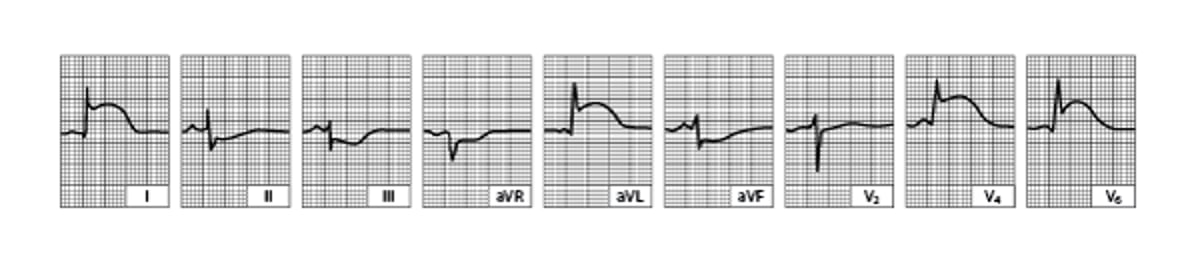

For STEMI, initial ECG is usually diagnostic, showing ST-segment elevation 1 mm in 2 or more contiguous leads subtending the damaged area (see figure Acute Lateral Left Ventricular Infarction).

Acute Lateral Left Ventricular Infarction (tracing obtained within a few hours of onset of illness)

There is striking hyperacute ST-segment elevation in leads I, aVL, V4, and V6 and reciprocal depression in other leads.